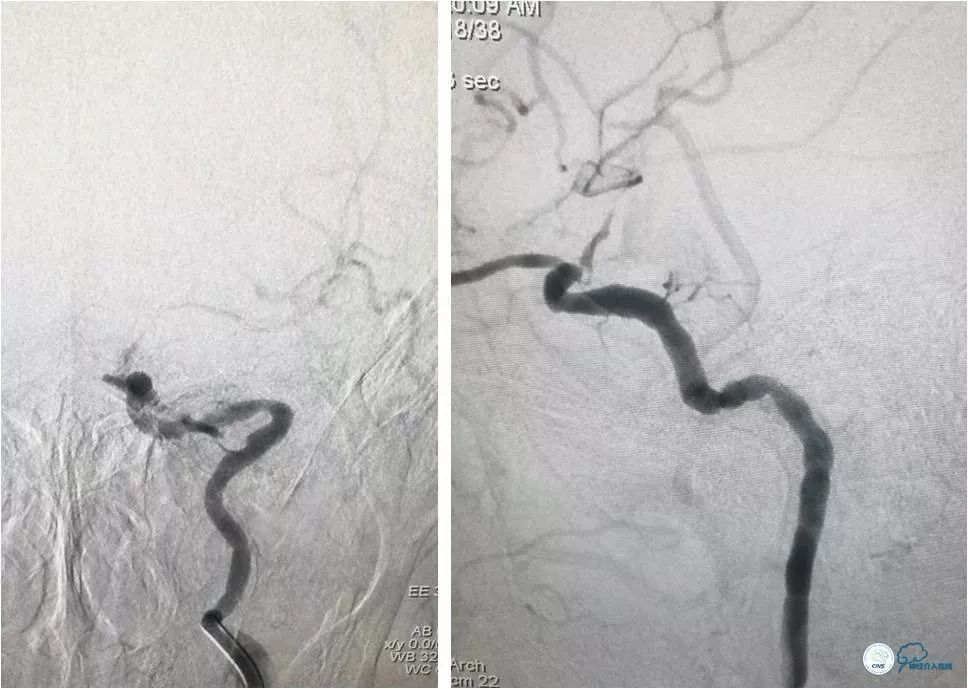

全麻下右股动脉入路,8F导引导管至左颈总动脉末端,将6F Navien导管送至左颈内动脉C1段以远,造影示左颈内动脉C6-7段长段狭窄,狭窄率约90%,长度约10mm(图7)。

图7

路径图下沿Navien导管送入Echelon 10微导管携Synchro微导丝(0.014″,200cm)尝试过狭窄段未成功(图8)。

图8